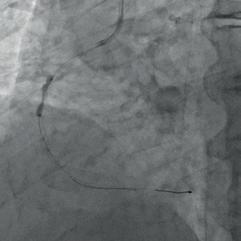

Figure 3a: Repeated dilatation with the NC balloon.

Figure 3b: RCA treated with an IVL balloon.

Figure 3c: RCA dilatation with a NC balloon after IVL. Figure 4: Final result after stent implantation.

mospheres, the balloon ruptured, resulting in abrupt vessel occlusion and haemodynamic deterioration of the patient with hypotension and bradycardia. After medical stabilisation, flow was partially restored through the RCA with a clearly visible large dissection flap in the middle portion of the vessel (Fig. 2c). The patient was clinically stabilised and the procedure was terminated. A few months later we decided to do a second procedure. This time we found a marked deterioration of the RCA, which was critically stenosed in a mid-portion. After a difficult wire crossing, multiple dilations were performed with different semi-compliant and non-compliant balloons throughout the RCA (Fig. 3a). We then decided to treat the lesion with intravascular lithotripsy, but the IVL balloon failed to cross the lesion. Subsequently,

the entire middle RCA was treated by multiple dilations with smaller OPN NC balloons (2.0  15 mm and 2.0  10 mm, applied >30 inflations at 35 – 40 atmospheres) in order to create space for IVL balloon delivery. After these aggressive dilations, a 3.0  12 mm IVL balloon (Skockwave) was finally advanced and multiple (80 in total) intravascular pulses were delivered throughout the middle RCA (Fig. 3b) with improved angiographic appearance. After partial dissection of the severely calcified stenosis, we performed additional inflation with non-compliant 2.5  15 mm and 3.0  20 mm balloons (Fig. 3c) and finally achieved a satisfactory result.